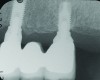

Fig 7 through Fig 14. Periapical radiographs of a 62-year-old woman who received a fixed porcelain-fused-to-metal reconstruction supported by abutments by internally connected dental implants. Fig 7 through Fig 10 are at initial prosthesis placement: mandibular site Nos. 30 and 29 (Fig 7); mandibular site Nos. 26, 25, and 23 (Fig 8); mandibular site Nos. 23 and 21 (Fig 9); mandibular site Nos. 21 through 19 (Fig 10). Fig 11 through Fig 14 are 11 years later (2013) and show excellent preservation of the vertical bone levels around the implants: mandibular site Nos. 30 and 29 (Fig 11); mandibular site Nos. 26 and 25 (Fig 12); mandibular site Nos. 25 and 23 (Fig 13); mandibular site Nos. 20 and 19 (Fig 14). It is interesting to note that in the mandibular right posterior quadrant there is a matched pair, ie, an external hex dental implant (No. 30) adjacent to an internally connected dental implant (No. 29). The bone levels around each of these designs are well-preserved at the 11-year follow-up.

Figure 10

Figure 11

Figure 12

Figure 13

Figure 14